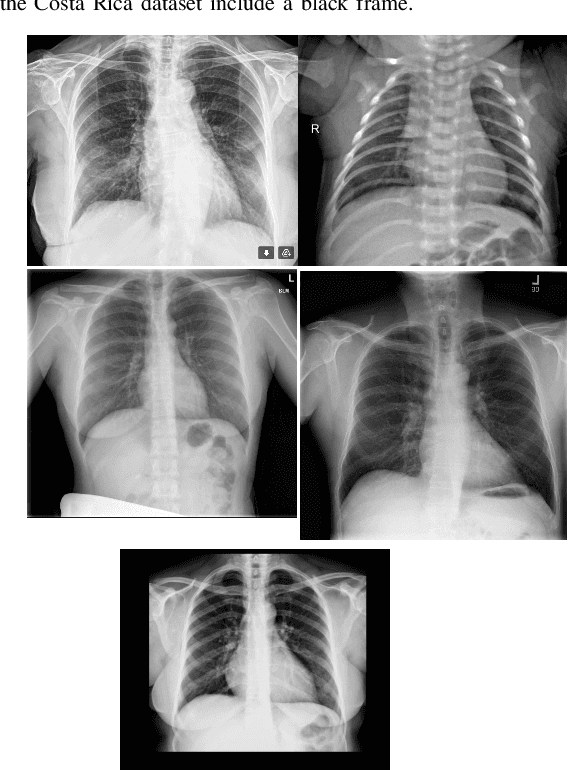

Abstract:The Corona Virus (COVID-19) is an internationalpandemic that has quickly propagated throughout the world. The application of deep learning for image classification of chest X-ray images of Covid-19 patients, could become a novel pre-diagnostic detection methodology. However, deep learning architectures require large labelled datasets. This is often a limitation when the subject of research is relatively new as in the case of the virus outbreak, where dealing with small labelled datasets is a challenge. Moreover, in the context of a new highly infectious disease, the datasets are also highly imbalanced,with few observations from positive cases of the new disease. In this work we evaluate the performance of the semi-supervised deep learning architecture known as MixMatch using a very limited number of labelled observations and highly imbalanced labelled dataset. We propose a simple approach for correcting data imbalance, re-weight each observationin the loss function, giving a higher weight to the observationscorresponding to the under-represented class. For unlabelled observations, we propose the usage of the pseudo and augmentedlabels calculated by MixMatch to choose the appropriate weight. The MixMatch method combined with the proposed pseudo-label based balance correction improved classification accuracy by up to 10%, with respect to the non balanced MixMatch algorithm, with statistical significance. We tested our proposed approach with several available datasets using 10, 15 and 20 labelledobservations. Additionally, a new dataset is included among thetested datasets, composed of chest X-ray images of Costa Rican adult patients